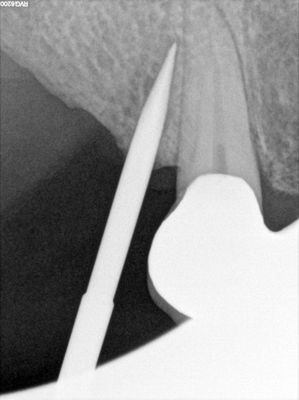

Mtiu - implant with bone expansion and graft

13 root is angled apex to the distal, 14 osteotomy positioned in region of thin bone, prepared to just under 2mm, remainder with densah drills, implant placed with bone around it countersunk. buccal region grated with sticky bone from 50/50 Mineralized cortical/cancellous followed by collagen membrane soaked in prf fluid, additional fibrin membrane overtop.